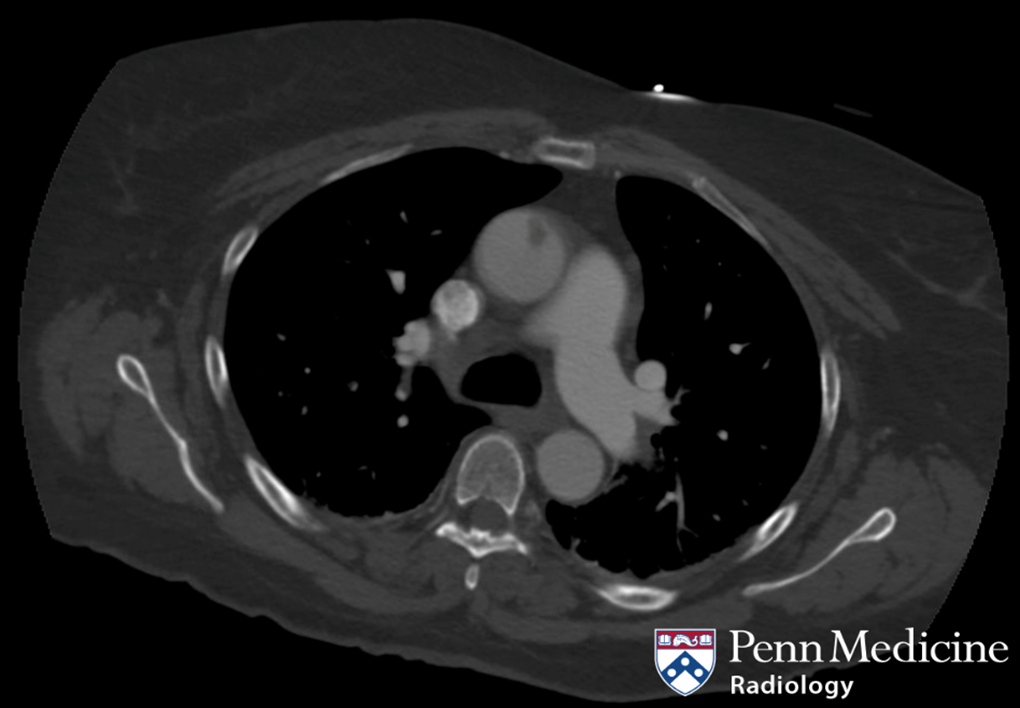

Cases of the Week

Check out our Cases of the Week!